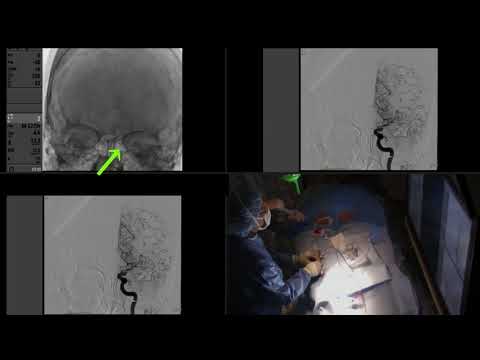

Hellow guys, Welcome to my website, and you are watching Open Repair of a Superior Mesenteric Artery Aneurysm (Balazs Lengyel MD, Alan B. Lumsden MD). and this vIdeo is uploaded by Houston Methodist DeBakey CV Education at 2024-10-10T10:28:12-07:00. We are pramote this video only for entertainment and educational perpose only. So, I hop you like our website.